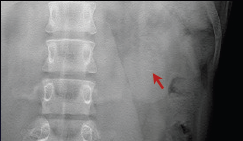

断层容积图片:

影像描述: X线平片:立位X线腹部平片可疑盆腔内(左侧)点状高密度影,但由于肠道气体影响,双肾影无法显示(患者不愿意接受清洁灌肠)。 断层容积图像:去除了肠道气体的影响,清晰显示盆腔内(左侧)点状高密度影,同时显示左肾中部多发点状高密度影。 断层容积诊断: 左侧输尿管盆内段结石,左肾多发结石。 病例点评: 清洁灌肠,是怀疑泌尿系结石时X线腹部平片检查前的常规准备,许多患者不愿意接受这种暴露,接触敏感部位的检查,清洁灌肠也会给患者带来很大的痛苦。断层容积成像完全不需要清洁灌肠准备。肾结石,输尿管下端结石同时显示,说明断层容积成像能大范围清晰显示病变。